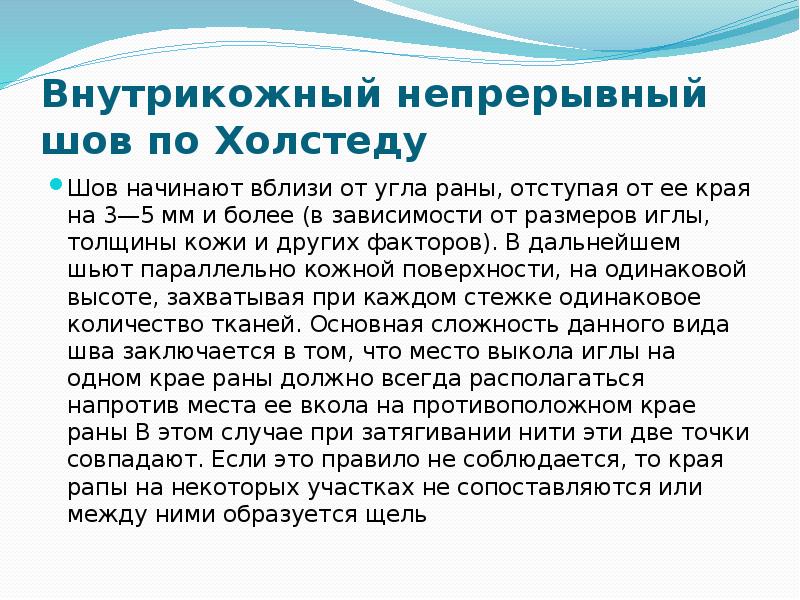

- 50. Внутрикожный непрерывный шов по Холстеду Шов начинают вблизи от угла раны,